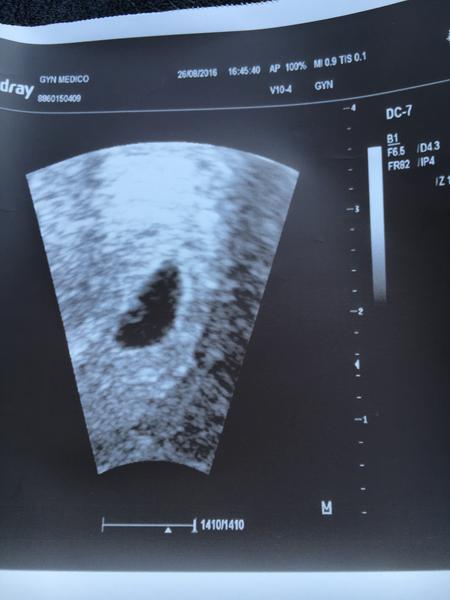

@ms.neomagic tohle je soukromá klinika Gynmedico, v patek ta doktorka super - Sestinova... Dneska Tomilova a hruza...

@simi1510 jako promiň co teď řeknu, ale ta doktorka je normální kr.va, protože progres samozřejmě je. Dneska krásná bublinka a už vidím i náznak plodu. Pokud byla ovulace až takhle pozdě, tak všechno sedí. Samozřejmě můžeš potratit, to je něco co se stane když to nečekáš a těhotenství od začátku šlape a vyvíjí se a stejně v 9tt konec. Ale teď bych se nestresovala, i když mě se to mluví, chápu jak se cítíš. Mě nervovali vždycky všichni taky a nikdo nechtěl chápat, že mám ovulaci až skoro o týden později. HCG ti neřekne nic, musela bys chodit každé dva dny a i tak to nepoznáš. Vydržela bych týden do dalšího ultrazvuku a tam se už uvidí. držím palce (hug) není tu objímající smailík 🙂

@denikzaslouzilemamy na tom druhem vidis náznak? Ja se v tom vubec nejak nevyznám a proti patku mi prijde, ze je to mensi a tu bublinku tam nevidim :-/

@simi1510 aha, já myslela, že ten první je z dneška ☹ každý doktor má jiný utrazvuk, takže pokaždé bude i jiná kvalita. Vím, že je to hrozné, ale ty dva týdny budeš muset vydržet ☹

@denikzaslouzilemamy debilni ruska... Ze misto 7+2 dle ms to odpovídá 5.tydnu